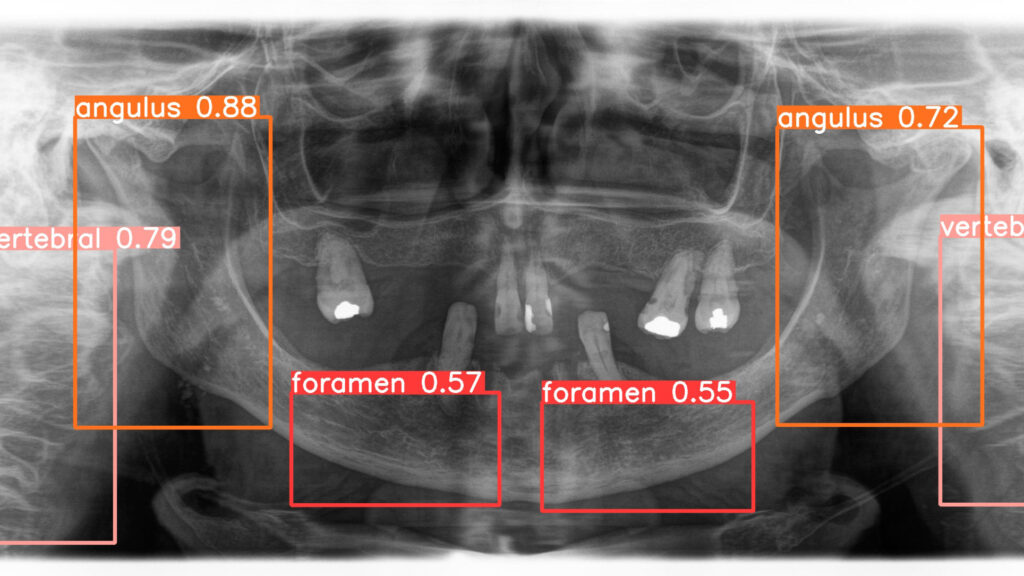

Panoramic radiographs, a cornerstone of dental diagnostics, are widely used by dentists and oral and maxillofacial (OMF) surgeons in routine clinical practice. While radiologists may occasionally interpret these images, OMF surgeons frequently analyze their own panoramic radiographs. Research highlights that a clinician’s training significantly influences the accuracy of radiographic interpretation. In dentistry, diagnostic performance varies due to differences in individual knowledge, skills, and biases, leading to inconsistencies in assessing radiographic images. This variability can result in misdiagnosis or mistreatment, with studies indicating that misdiagnosis rates for caries depth in conventional radiographs can reach 40%, and 20% of teeth may be incorrectly identified as diseased. These challenges underscore the potential for AI to enhance diagnostic precision and reduce errors in dental practice (Fig. 1).

Fig. 1